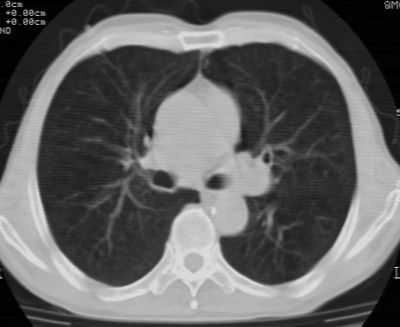

标题: CT24783:m71,既往肺心病史3年,现咳嗽,憋喘。 [打印本页]

标题: CT24783:m71,既往肺心病史3年,现咳嗽,憋喘。

1、左肺上叶spn,毛刺+分叶+血管集束征,考虑周围型肺癌可能性大

2、全小叶性肺气肿。

1)左肺上叶周围型肺癌可能。2)两肺全小叶型肺气肿。

左上周围型肺癌,全小叶型肺气肿。